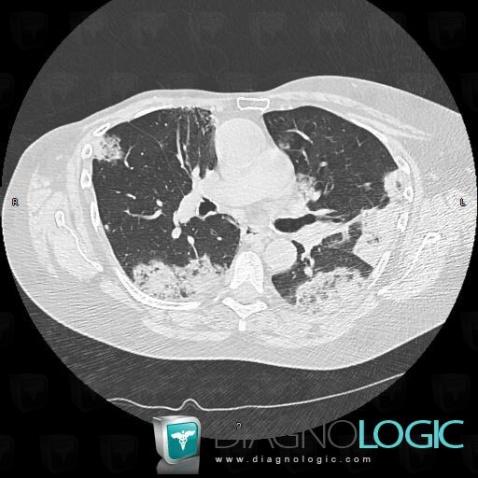

Bronchioloalveolar carcinoma, Pulmonary parenchyma, CT

Here is the specific information in the key image above:

- Diagnosis Bronchioloalveolar carcinoma, Location(s) Pulmonary parenchyma, with gamuts Multiple pulmonary nodule